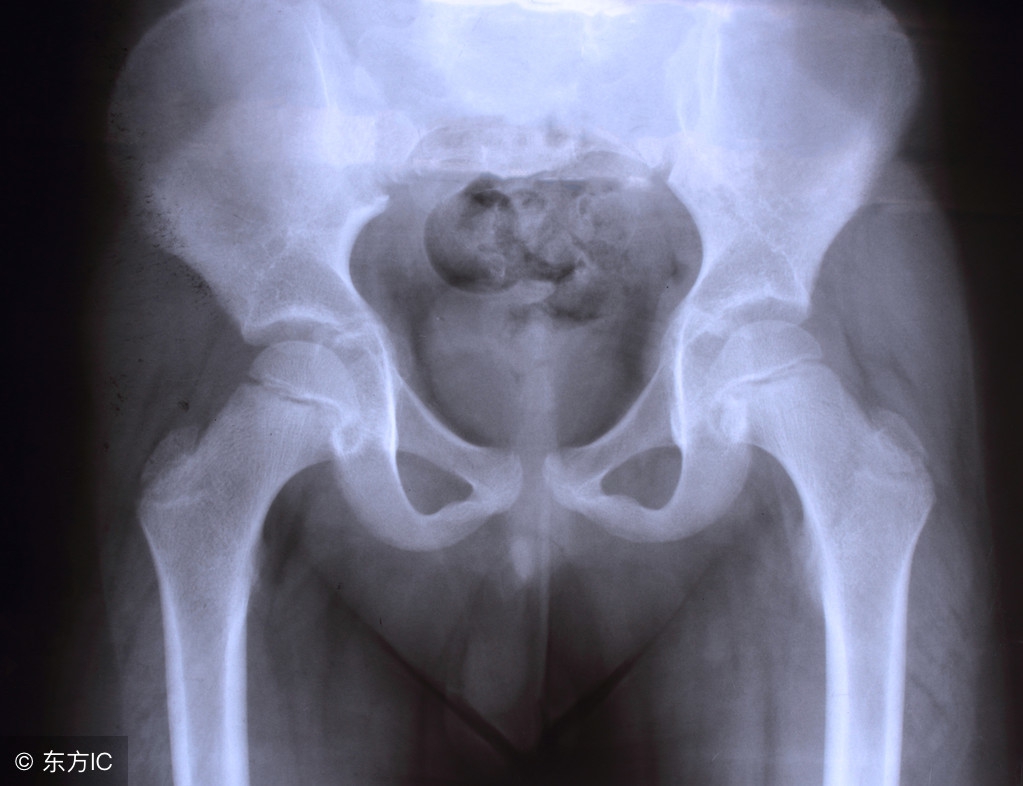

盆腔痛是妇女常见的症状之一,尤其是慢性疼痛。从临床上看,盆腔痛发病复杂,找到病因很难,而且疼痛程度与病变程度还不一定成正比。所以了解女性慢性盆腔痛的症状和治疗就显得尤为重要。

三、慢性盆腔痛有哪些治疗方法?

2.腹腔镜治疗